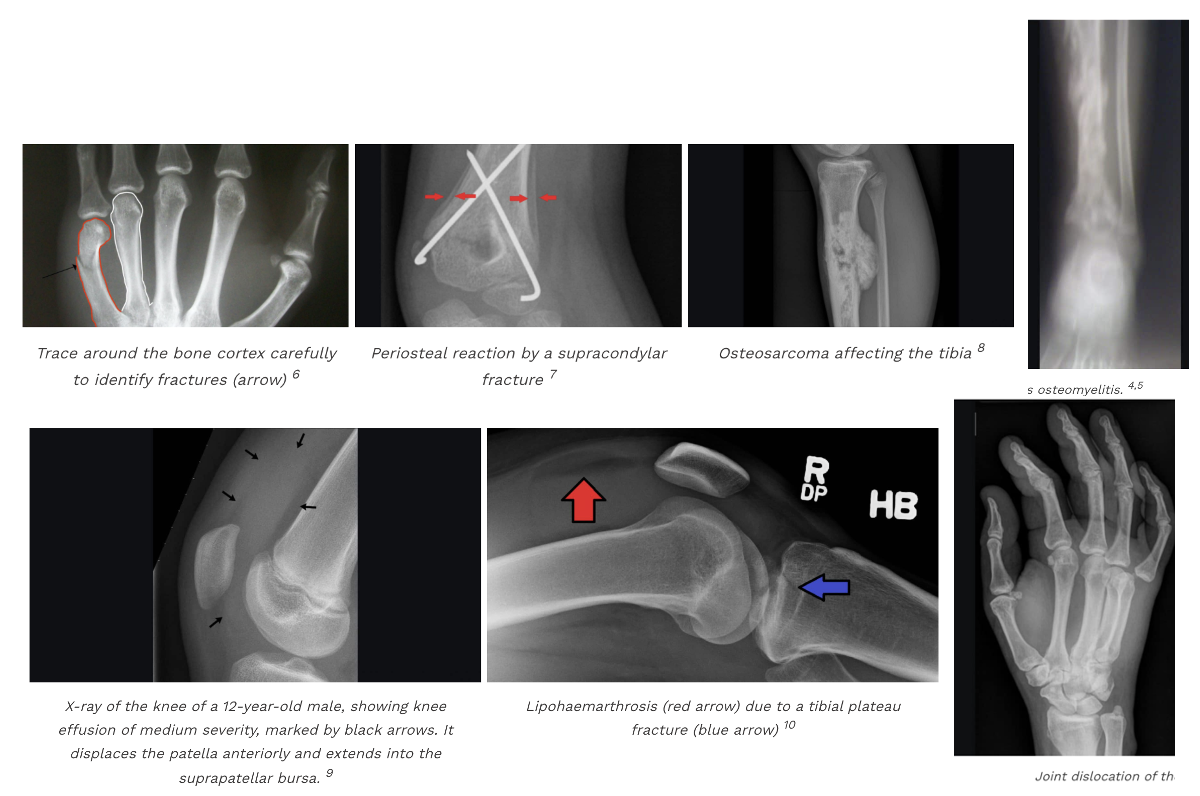

How do you approach an MSK X-ray?

Describing a fracture on XR approach?

MSK X-RAY APPROACH:

General:

ABCS approach: Alignment & joint space, Bone texture, Cortices, Soft tissues

DESCRIBE A FRACTURE:

Where - what bone? location (proximal, middle, distal OR epiphysis, metaphysis, diaphysis)? Does it involve articular surface (intra/extra-articular)?

Types:

1. Simple vs Compound:

2. Subtype:

Displacement - describe the position of distal fragment to body (anterior/posterior)

OVERALL: 1) Type (simple/compound > subtype) 2) Relevant region, side and name of bone 3) Displacement (& angulation, translation)